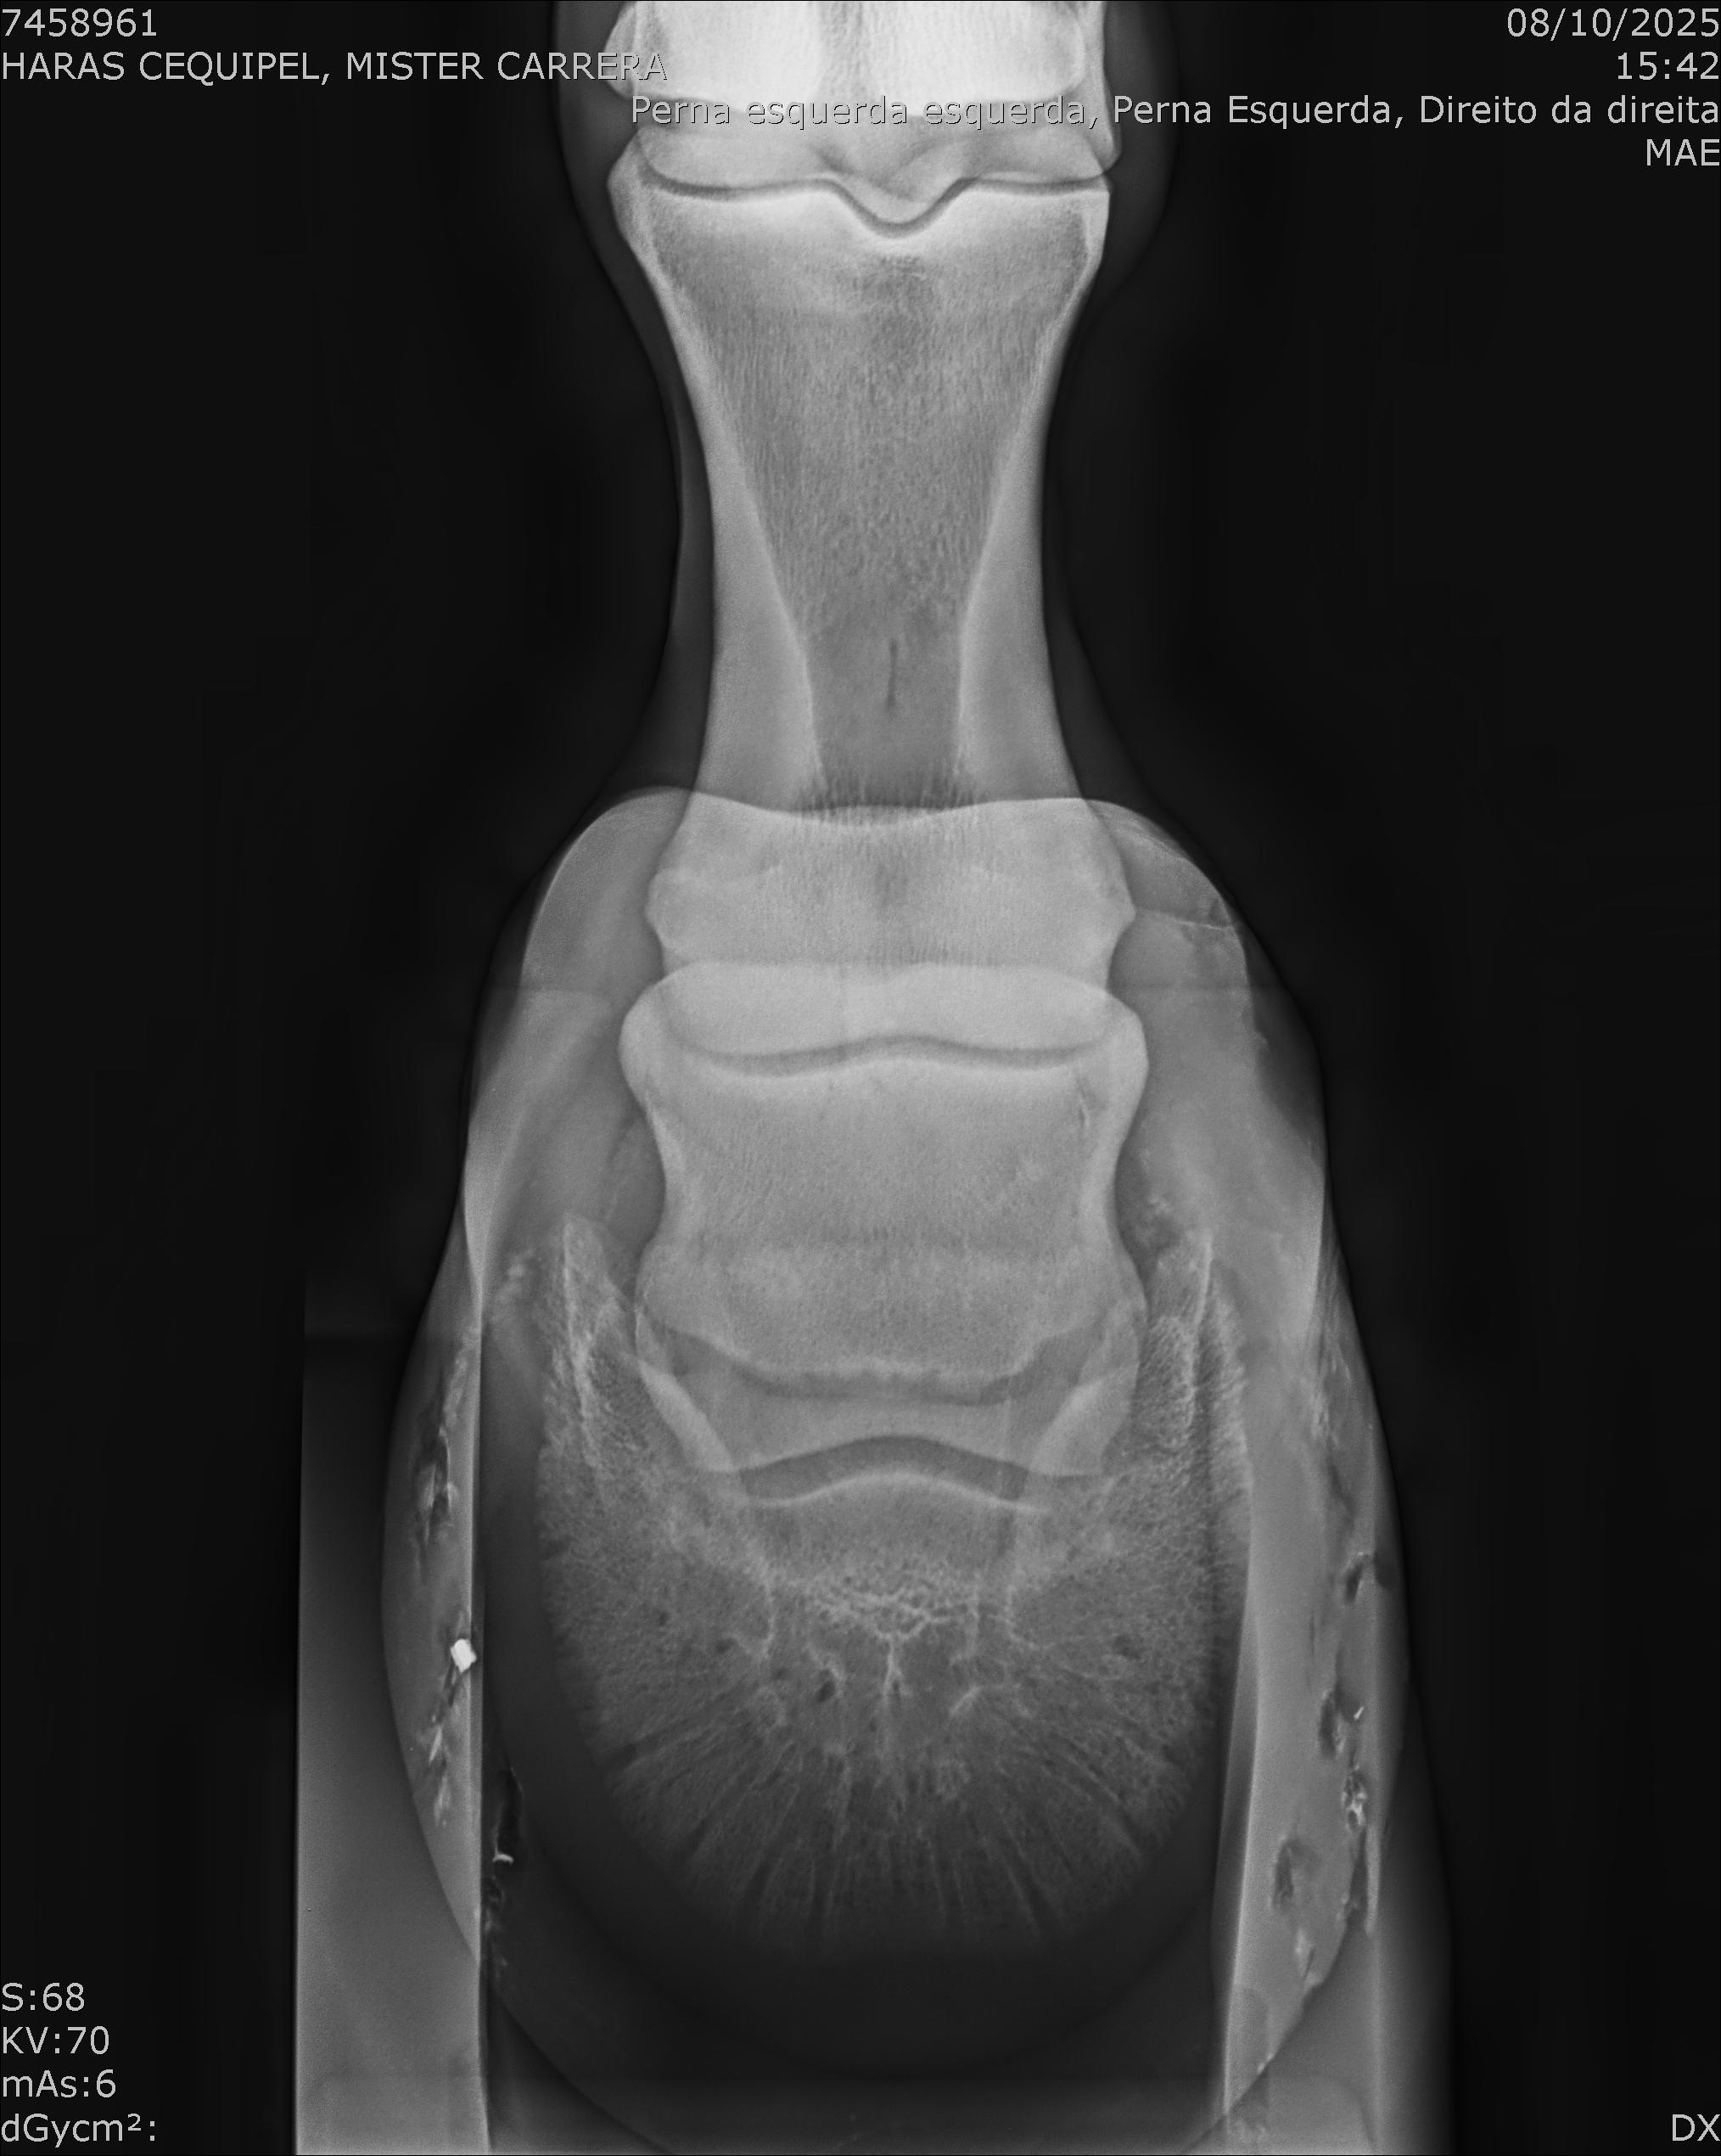

:: RAIOS-X DO LOTE